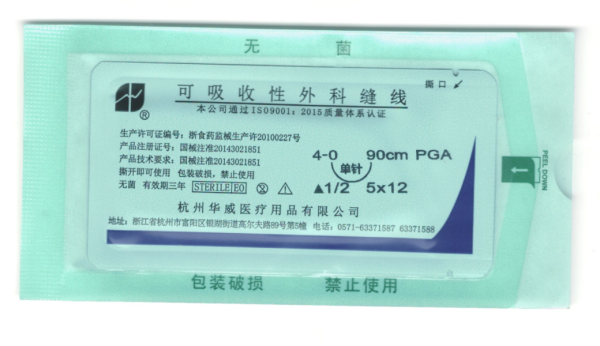

可吸收性外科縫線

杭州華威醫療用品有限公司地處滬、杭、甬“金三角”的交匯點,景色秀麗的富春江畔,占地10萬平方米,項目總投資8000萬元,是國家食品藥品監督管理局定點生產醫療器械的專業廠家。

公司主要生產經營各種醫用縫合針,醫用縫合線,手術刀片,醫用內窺鏡,微創手術器械等系列產品。產品規格齊、品種全,廣泛應用于普外科、整形外科、顯微外科、五官科、肛腸科、婦科、骨科、泌尿科、胸科、腦科等手術領域。產品暢銷全國20多省市并遠銷全球多個國家和地區,深受海內外客戶的贊譽。華威生產經營有20多年的歷史,全國擁有近1000家客戶。